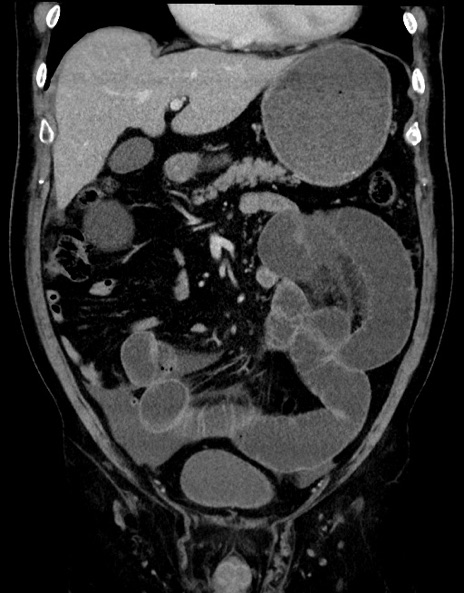

症例15(冠状断像)

【症例】70歳代男性

【主訴】腹痛

【現病歴】今朝から腹痛あり。全体的に痛い。特に左上の方。排ガスが今日はない。冷や汗が出る。

【既往歴】直腸癌術後

【身体所見】左側腹部〜上腹部に圧痛あり。腹膜刺激症状明らかなではない。軽度反跳痛。左下腹部に術後瘢痕あり。

【データ】WBC 7700、CRP 0.02